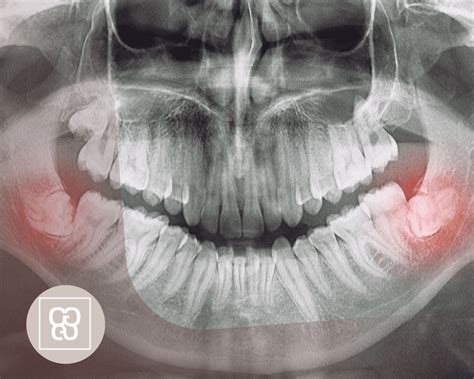

Evaluación previa: Antes de programar la cirugía, examinaremos tu boca y tomaremos radiografías panorámicas o 3D. Así podemos ver la posición de las muelas del juicio y su relación con el hueso, los senos maxilares (en el caso de superiores) o el nervio dentario inferior (en el caso de inferiores). Con esta información, planificamos la extracción de la forma más segura.

La facilidad o dificultad con la que tu dentista o cirujano maxilofacial puede extraer las muelas de juicio depende de su posición y desarrollo. El especialista tendrá una idea de qué esperar a partir de los exámenes preoperatorios. Un tercer molar que salió completo, normalmente se puede extraer con la misma facilidad que cualquier otro diente. Pero si está debajo de las encías, más incrustado en el maxilar, si puede requerir una incisión, eliminar una porción de hueso, por lo que requerirá un proceso de extracción más complicado.

Acceso a la muela: Si la muela del juicio ya salió parcialmente, simplemente la tomaremos con instrumentos especiales. Si está incluida o impactada (atrapada bajo la encía o el hueso), haremos una pequeña incisión en la encía para descubrirla. Es posible que necesitemos remover un poco de hueso alrededor o cortar la muela en partes para extraerla con mayor facilidad. Todo esto suena aparatoso, pero ten en cuenta que estarás anestesiado/a: no duele, aunque sí puedes oír el sonido de los instrumentos o notar vibración.

Lesión nerviosa (parestesia): Las muelas del juicio inferiores a veces están muy cerca del nervio dentario inferior (que da sensibilidad al labio y mentón) o del nervio lingual (sensibilidad de la lengua). En manos experimentadas, el riesgo de dañarlos es mínimo, pero puede ocurrir en extracciones complejas. Si un nervio se ve afectado, podrías notar adormecimiento, cosquilleo o pérdida de sensibilidad en el labio inferior, la barbilla o la lengua del lado de la extracción. Esto se llama parestesia. Antes de que te asustes: es extremadamente raro que sea permanente. En la mayoría de casos, esa sensación extraña es temporal y se resuelve en semanas o meses conforme el nervio se regenera. Tu cirujano oral probablemente habrá evaluado la posición de tus cordales con radiografías o un escáner 3D y, si veía un riesgo alto, habría tomado medidas especiales (como hacer una extracción parcial del diente para alejarse del nervio). ¿Cómo saber si te pasó? Cuando pase el efecto de la anestesia y, pasado un día, notes que sigues “dormido” de la mitad del labio o de la lengua. No duele, pero es una sensación molesta. Informa a tu dentista inmediatamente para hacer seguimiento. En la mayoría de casos, solo queda esperar y quizás recetar complejos vitamínicos que ayudan a la recuperación nerviosa. Con el tiempo suele volver la sensibilidad. Insisto, esto es muy poco común.